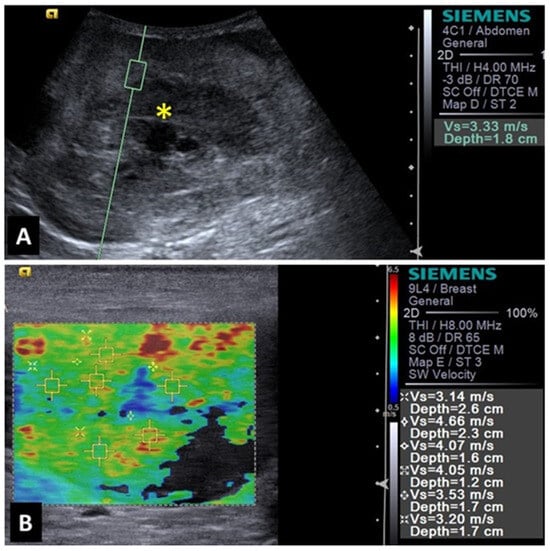

2.1. Mammary Glands

2.3. Spleen

2.5. Liver